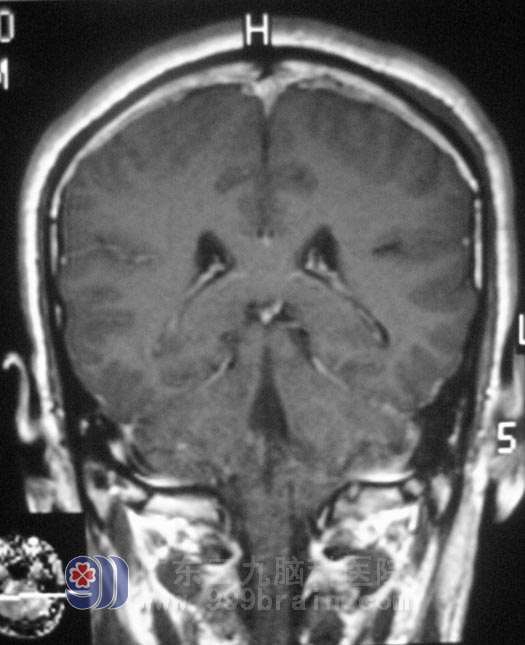

谢先生在一年前开始出现左耳听力变差,未行检查治疗,左侧听力进行性下降,伴间断性伴头痛,可忍受。头颅MRI结果提示:左侧桥小脑角区囊实性占位,考虑神经鞘瘤可能。

10月27日,广东三九脑科医院综合神经外科 鲁明主任主刀,在全麻下行左侧桥小脑角占位切除术+颅内压探头植入术,在显微镜下探查见桥小脑角鱼肉状肿瘤,包膜完整、血运丰富、质软、边界尚清,见肿瘤向前深入内听道,术中对三叉神经、后组颅神经等保护完好,手术顺利结束。术后病理结果为:(左侧桥小脑角区)神经鞘膜瘤。